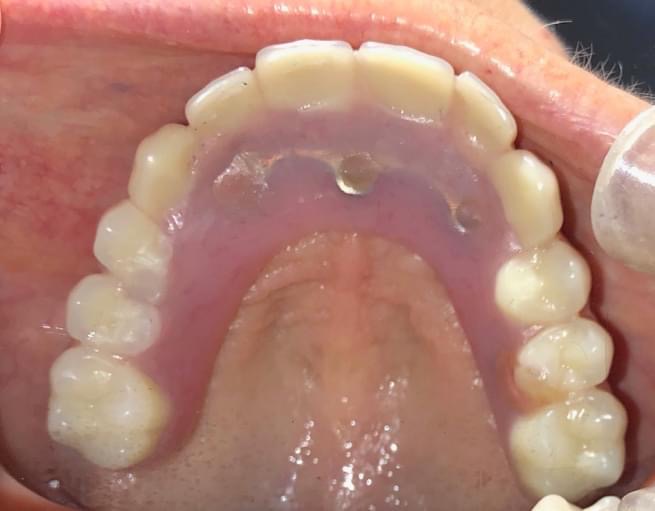

A dental implant is an option to replace a missing tooth. In this procedure, a small titanium screw is surgically implanted into the bone and allowed to set. The bone grows around it forming a tight connection, which additionally slows or stops the bone loss that occurs when the root of a natural tooth is missing. Once the implant is firmly set in the mouth, the dentist then works to attach the replacement tooth onto the top of the implant.

Dental implants are considered to be the most important advance in dentistry in the past 100 years. They allow us to predictably replace missing teeth in a very esthetically pleasing manner without compromising the integrity of the adjacent teeth and without the aid of removable appliances.